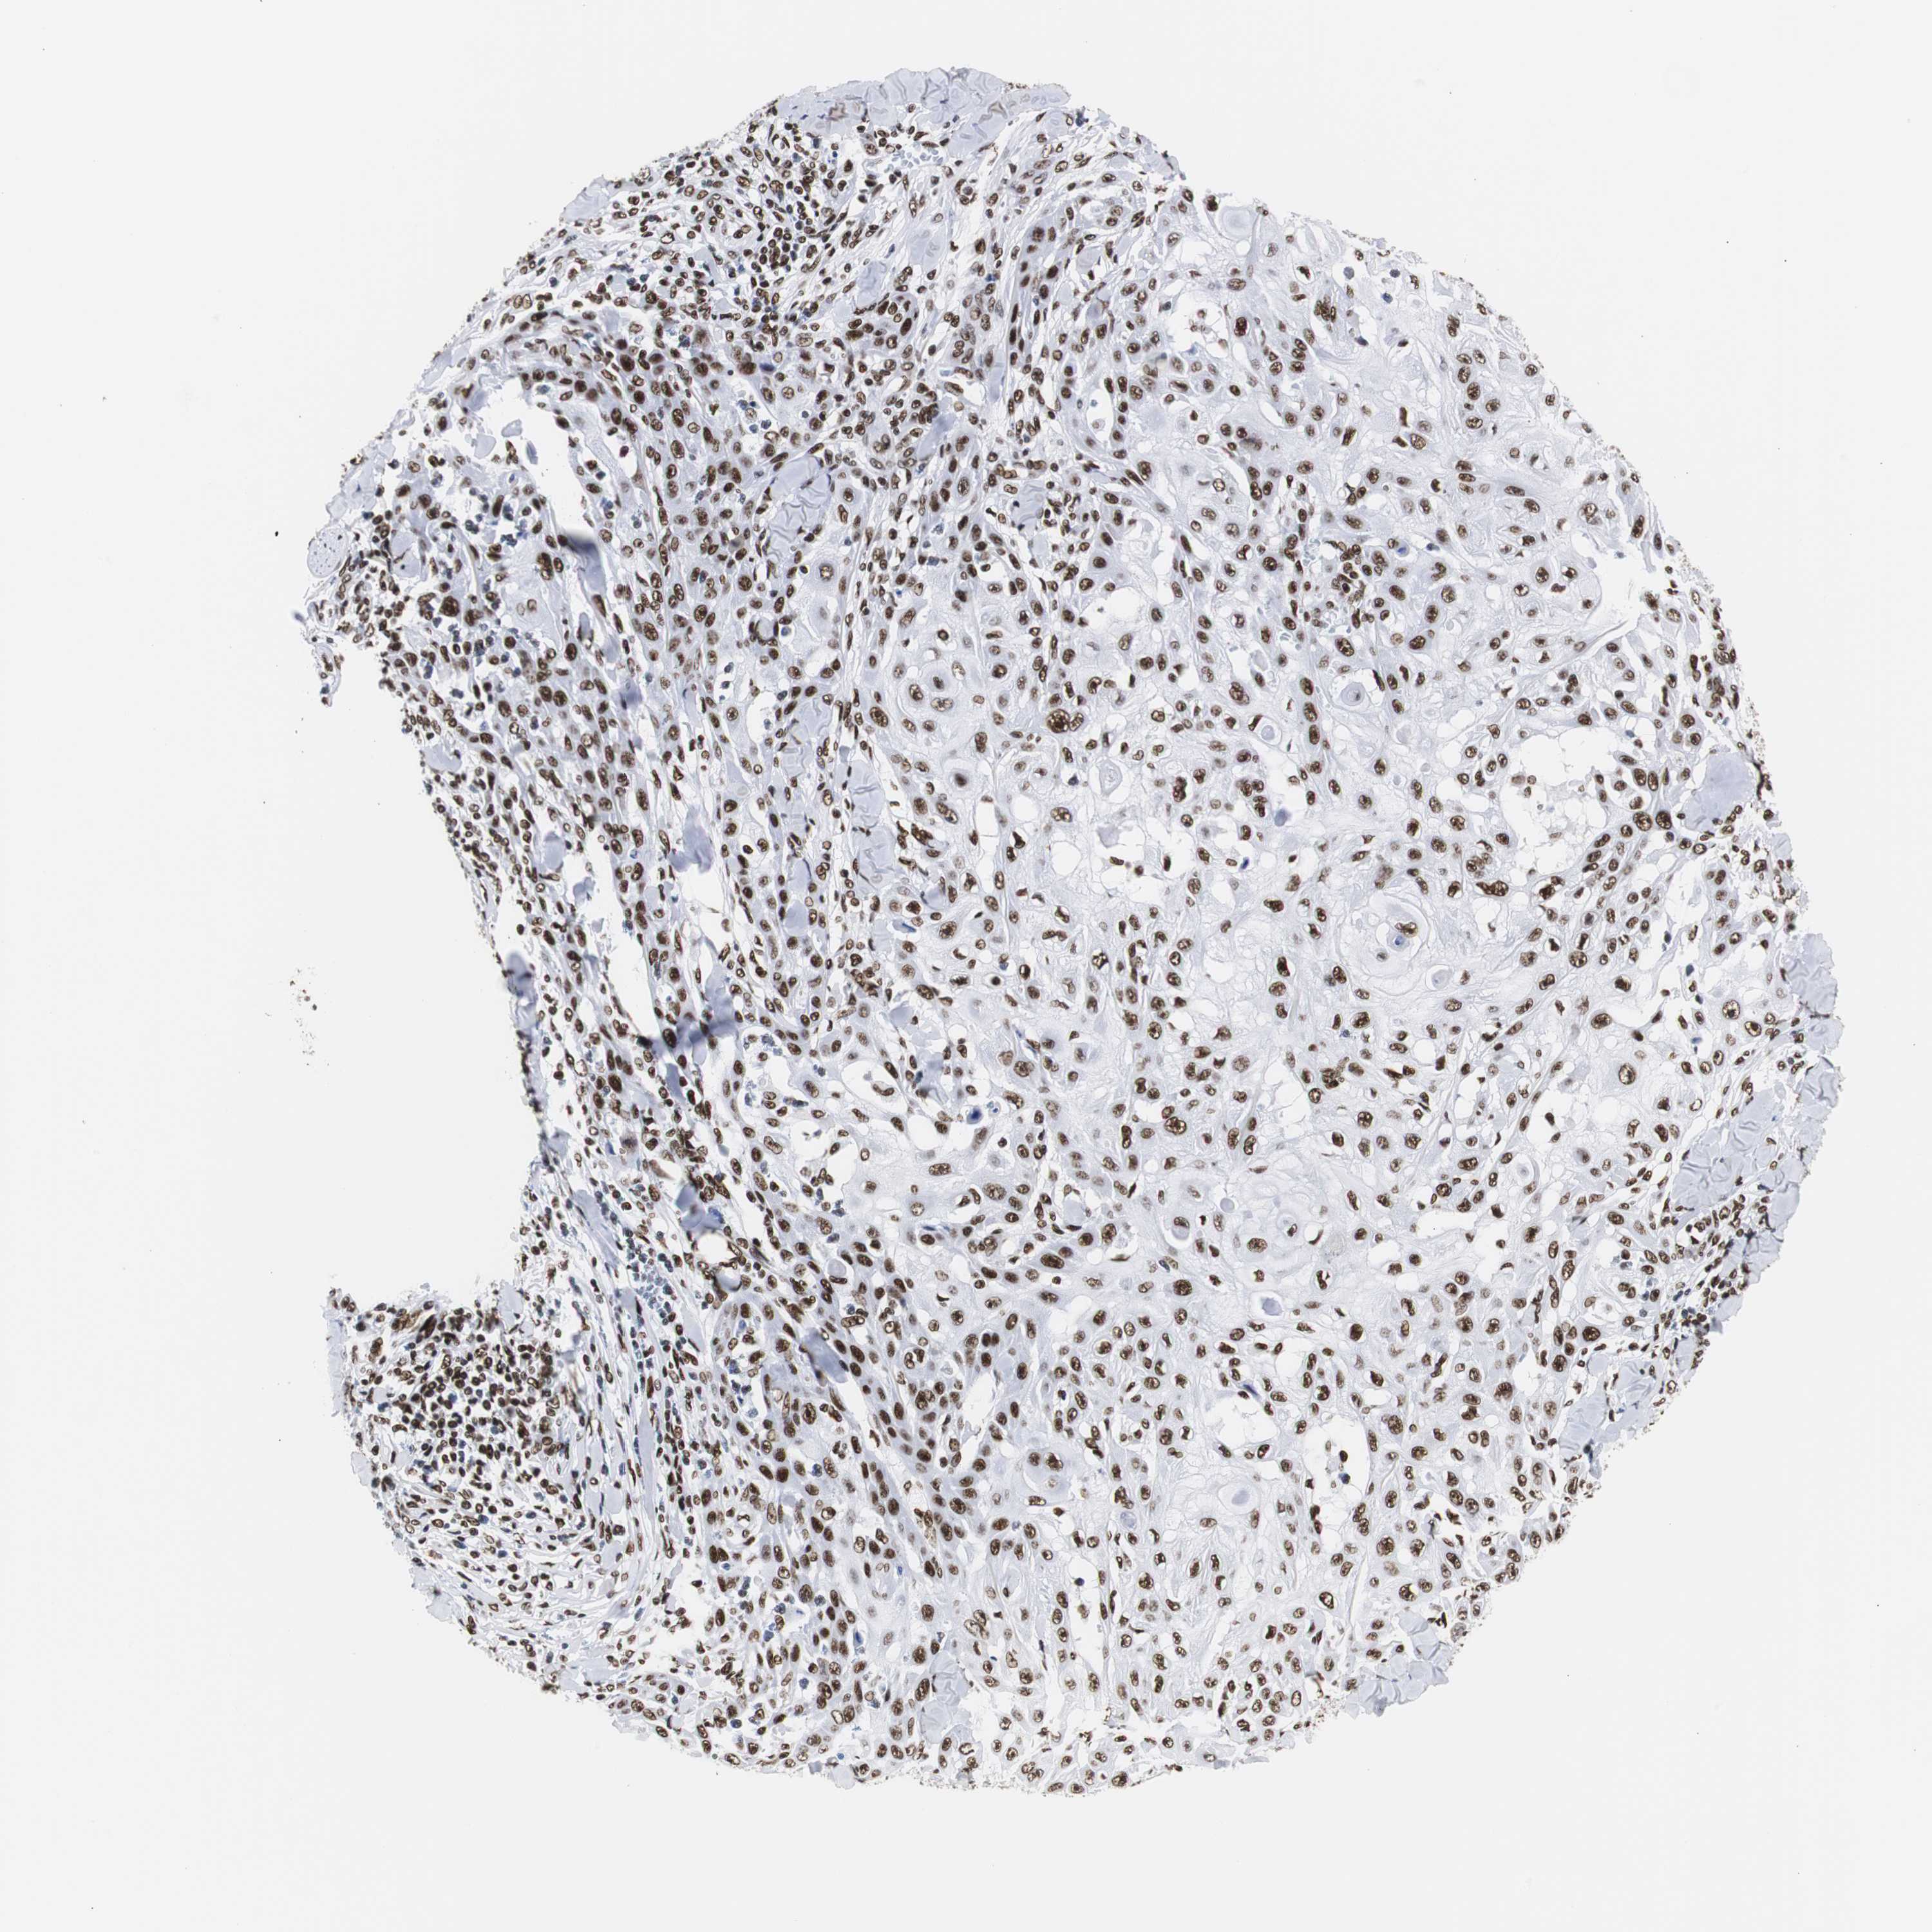

SKIN CANCER - Protein expressioni

A mouse-over function shows sample information and annotation data. Click on an image to view it in a full screen mode. Samples can be filtered based on level of antibody staining by selecting one or several of the following categories: high, medium, low and not detected. The assay and annotation is described here.

Each image is clickable and will lead to virtual microscopy that enables deeper exploration of all samples and also displays staining intensity scores, fraction scores and subcellular localization as well as patient and tissue information for each sample.

Antibody HPA016884

Staining

Medium

Moderate

75%-25%

Location

Nuclear

Squamous cell carcinoma, NOS